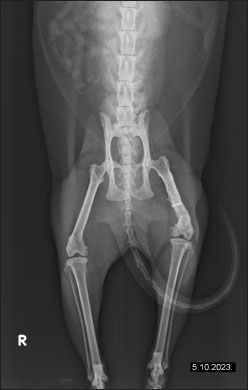

The owner reported continuous improvement, noting that the cat is increasingly bearing weight on the left hind limb, showing fewer signs of pain, and displaying an improved disposition. Follow-up radiographs revealed improvement in the condition of the femur post-therapy (Fig. 4). There is a noticeable improvement in bone structure, indicating enhanced healing and remodeling processes. After 2 months of intensive therapy and visible clinical improvement, the intervals between treatments were further extended. The radiograph shows the bone structure to be more consolidated, indicating effective recovery and remodeling (Fig. 5). Overall, the imaging suggests a positive outcome following treatment. In agreement with the owner, the treatments have continued on a monthly basis, and the cat continues to show progress.

Fig. 4. The radiographs of a cat’s left femur show (a) a ventrodorsal and (b) a mediolateral view demonstrating the femur after 1 month of LT, demonstrating reduced medullary transparency and early signs of bone consolidation.

Various clinical approaches have been explored to stimulate and accelerate bone healing, including physical stimulation, chemical treatments, and photostimulation. Photobiomodulation, the scientific term for LT, describes a photochemical process where light interacts with cells, triggering biochemical changes. The term is preferred as it reflects that some cellular processes are upregulated while others are downregulated. Numerous studies have examined photobiomodulation, many focusing on its cellular effects in vitro. Research highlights include increased angiogenesis, neurite extension, ion channel normalization, and cellular membrane stabilization. Moreover, LT promotes osteogenesis; both in vitro and in vivo studies demonstrate enhanced osteoblast proliferation, survival, and metabolism. The exact mechanisms behind photobiomodulation remain debated. Likely, multiple mechanisms exist depending on the target and cell type. The most recognized is the cytochrome c pathway in mitochondria, where cytochrome c, acting as a photoreceptor, absorbs light (500–1,100 nm). This excitation breaks nitric oxide bonds, enabling oxygen bonding and optimizing cytochrome c oxidase production. This enzyme is crucial for ATP formation, essential for cellular energy. The resulting ATP boosts secondary biological effects such as pain reduction, inflammation control, and tissue healing. LT also stimulates alkaline phosphatase activity and osteopontin, a protein crucial for osteoclast attachment to the mineralized bone matrix. Clinically, this leads to improved calcification and accelerated fracture healing.

Fig. 5. Radiographic evidence of consolidated bone structure and reduced medullary transparency following 25 sessions of LT.